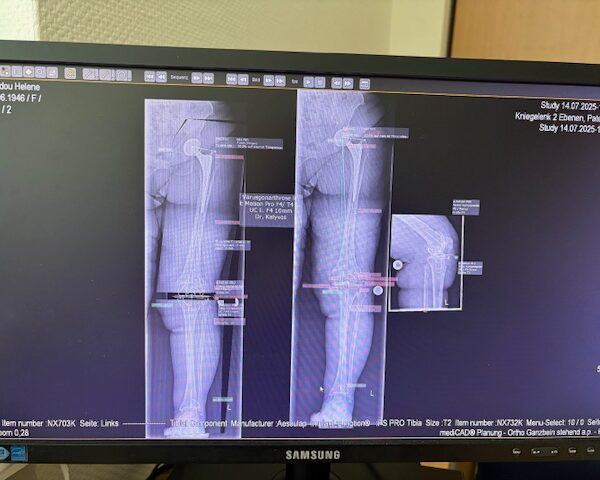

Ο προεγχειρητικός ψηφιακός σχεδιασμός

Πραγματοποιήθηκε σε ειδική ακτινογραφία ολόκληρων των δύο κάτω άκρων. Σε αυτό το ψηφιακό μοντέλο σχεδιάστηκε με ακρίβεια το είδος, το μέγεθος και η ακριβής θέση των προθέσεων, με βάση τα ανατομικά χαρακτηριστικά της ασθενούς.

Ο ψηφιακός σχεδιασμός επιτρέπει απόλυτη εφαρμογή των μοσχευμάτων, ελαχιστοποιώντας τα περιθώρια απόκλισης και εξασφαλίζοντας άριστη ευθυγράμμιση και κινηματική ισορροπία του γόνατος.

Τα εμφυτεύματα που χρησιμοποιήθηκαν στο γόνατο της ασθενούς είναι της Aesculap: E-Motion Pro, μηριαίο μέγεθος 4, κνημιαίο μέγεθος 4, με ενθέμα (inlay) 10mm.